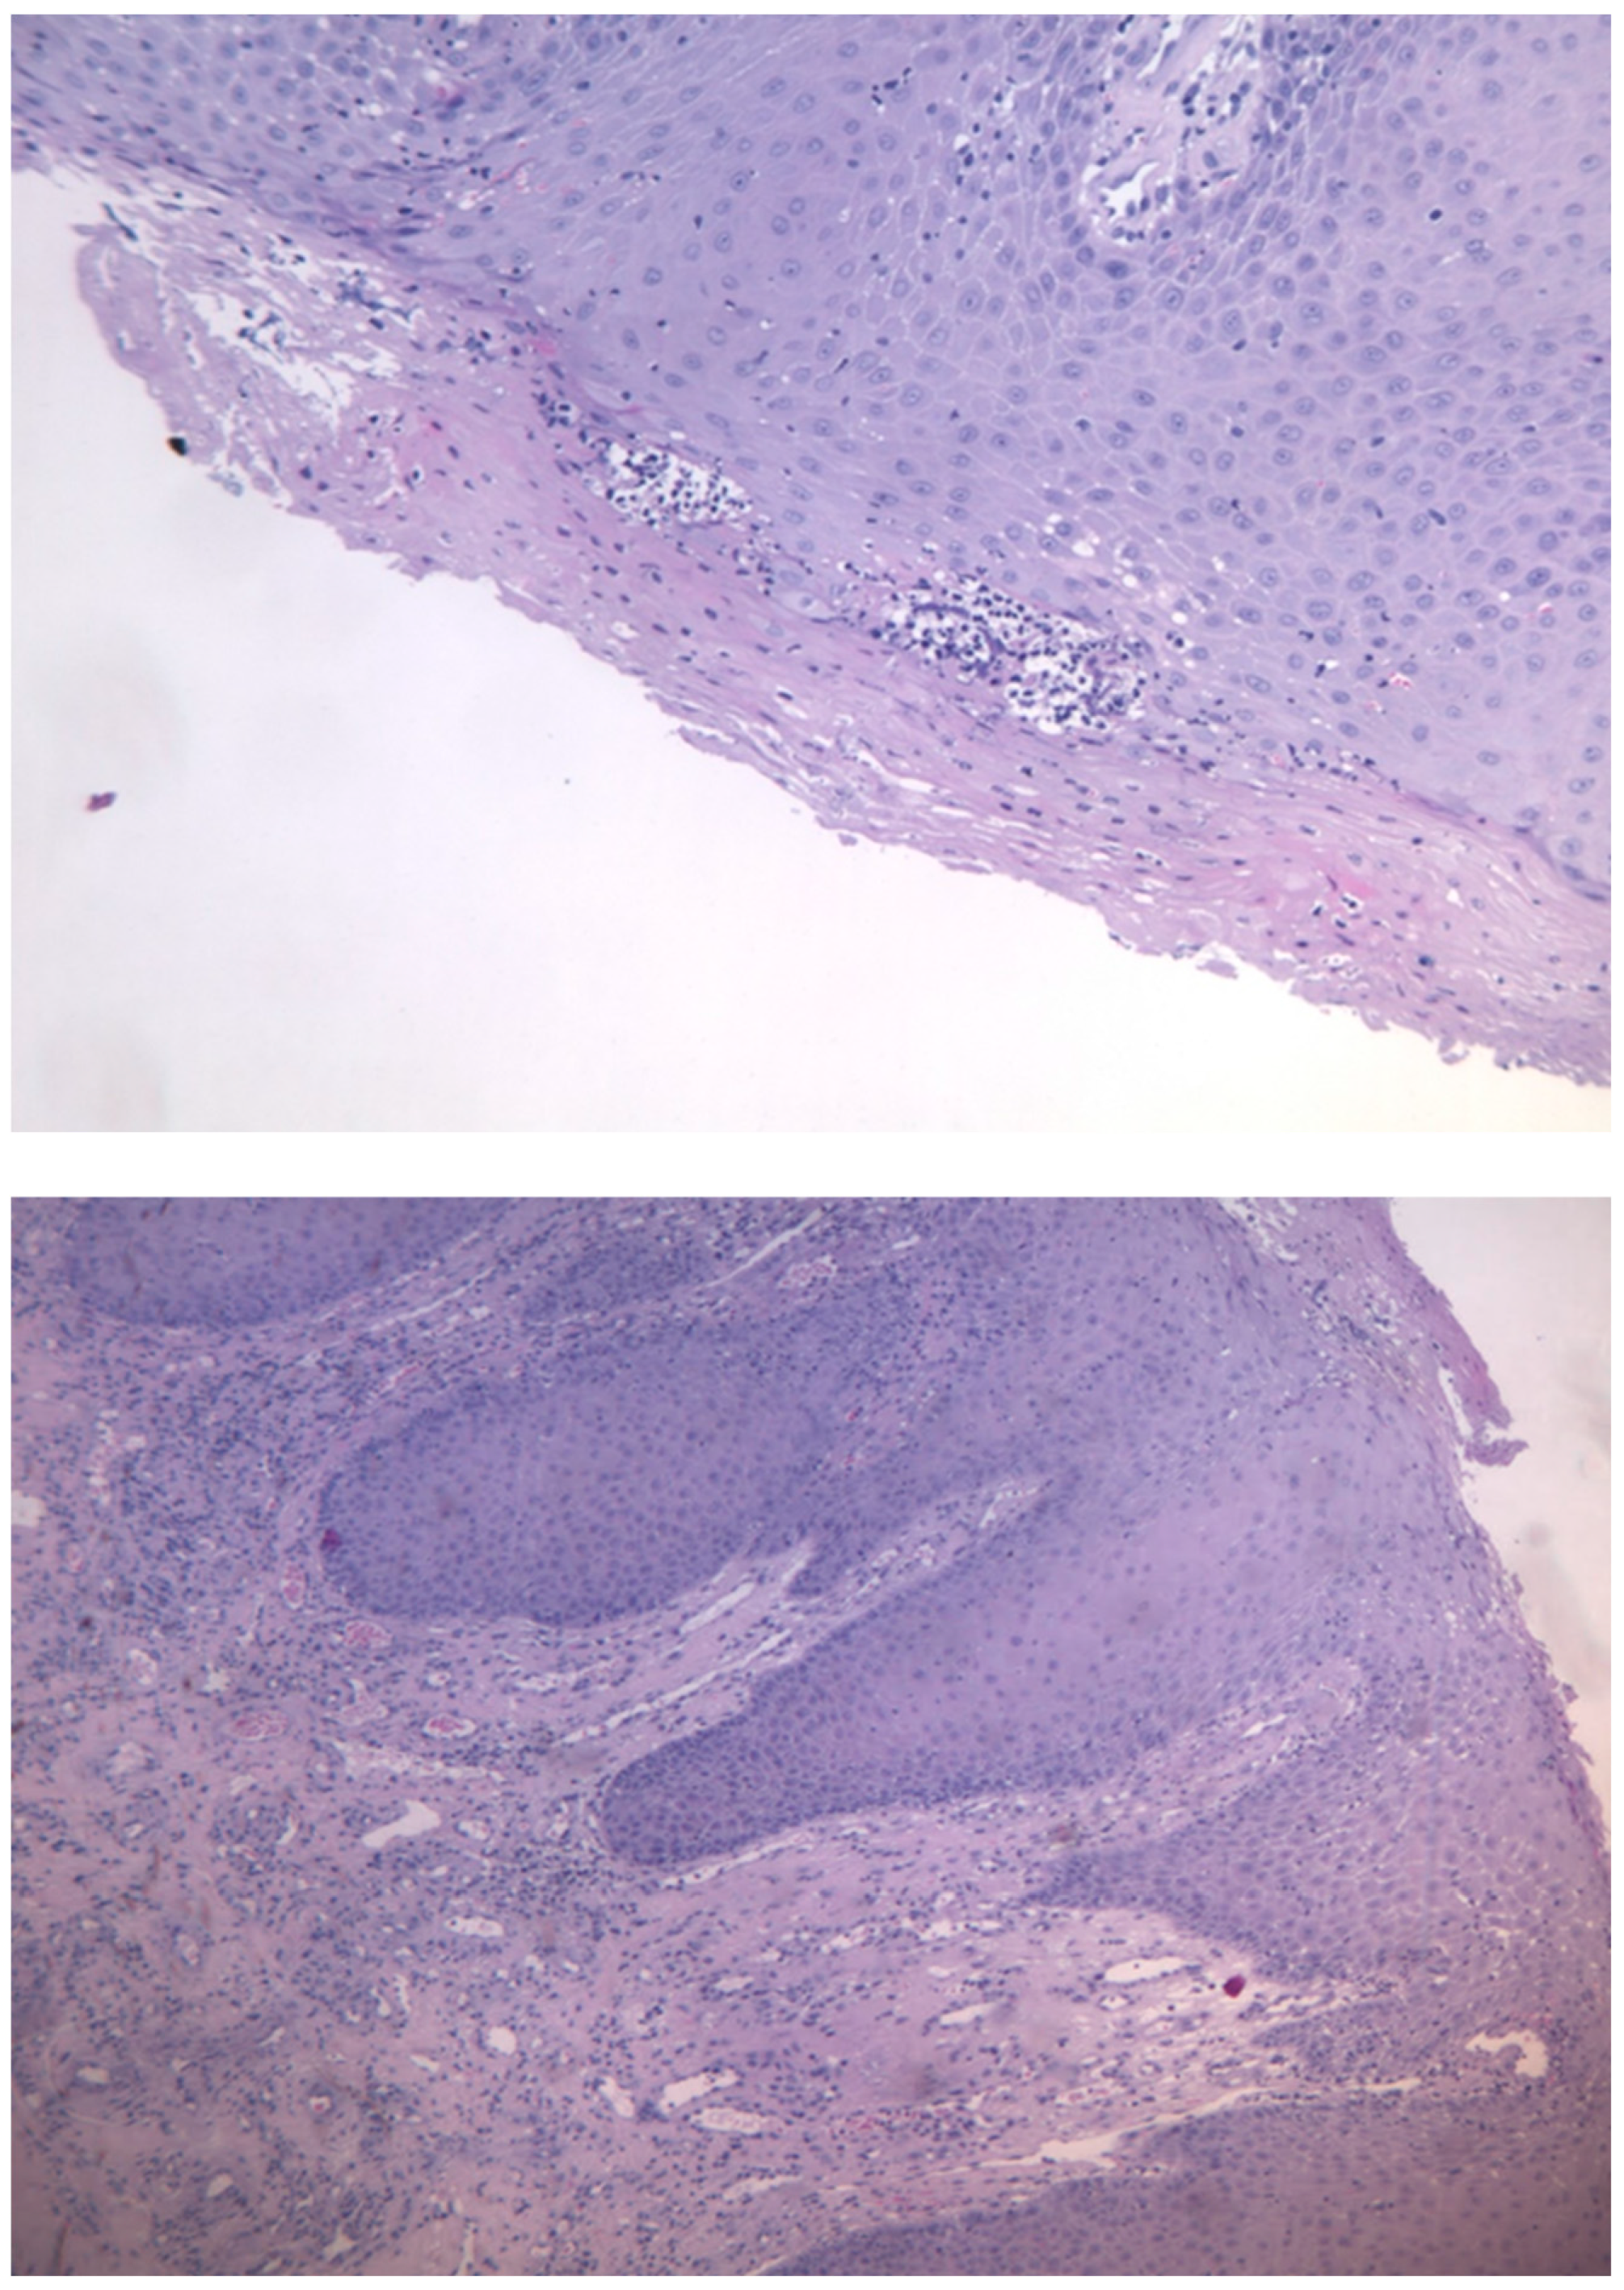

The histological examination described the presence of oral mucosa, partly covered by malpighian epithelium with mild hyperorthokeratosis, papillomatosis and neutrophil granulocytic exocytosis, and partly extensively ulcerated, with abundant granulation tissue in the submucosa, in absence of figures referable to neoplasia. (Figure 3a,b)

The histological aspect described by the anatomopathologist’s report was that of a partially ulcerated oral mucous membrane, partly covered by malpighian epithelium with mild hyperparakeratosis, acanthosis, focal spongiosis, papillomatosis, and lym-phocytic and neutrophil granulocytic exocytosis. In the corion there were numerous capillary vascular structures (CD31 +, CD34 +, actin MS +, actin ML +), coated by en-dothelial cells sometimes swollen, sometimes spindle,with indistinct limits, weakly eo-sinophilic cytoplasm and round nucleus. These vascular structures were organized in a lobular/glomeruloid type growth pattern and were present also in the muscle tissue in-cluded in the withdrawal. There was also an inflammatory infiltrate mainly of neu-trophil granulocytes and fibrin thrombi in the context of capillary lumens. This mor-phological and immunohistochemical description was compatible with kaposiform hemangioendothelioma. The case was discussed at the HEAD-NECK tumor board and it was decided collectively to proceed with a surgical treatment in order to extend the tumor resection margins.

Figure 3. a,b: Histological section with evidence of malpighian epithelium with mild hyperorthokeratosis.